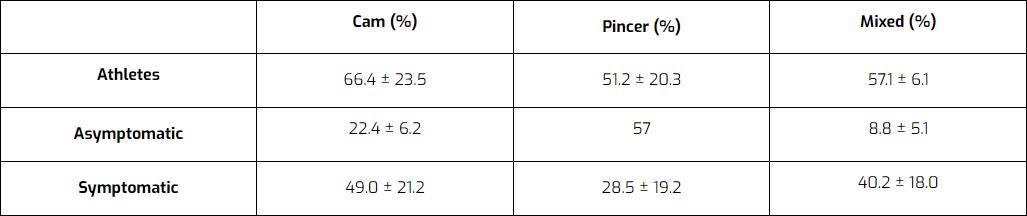

有人认为,这种形态的形成是对青春期需求的特殊适应。 可能是生长板移位导致头部变小变圆,但却变大了。 一旦生长板闭合,形态就不会再发生变化。 FAI 形态常见于无症状者,甚至 50-70% 的运动员。 因此,很多人都有异常,但只有一小部分人会出现疼痛。

评论者 Mascarenhas 等人 (2016)列出了在运动员、无症状和有症状人群中,Cam、Pincer 或混合形态 FAI 患者的百分比。 调查结果